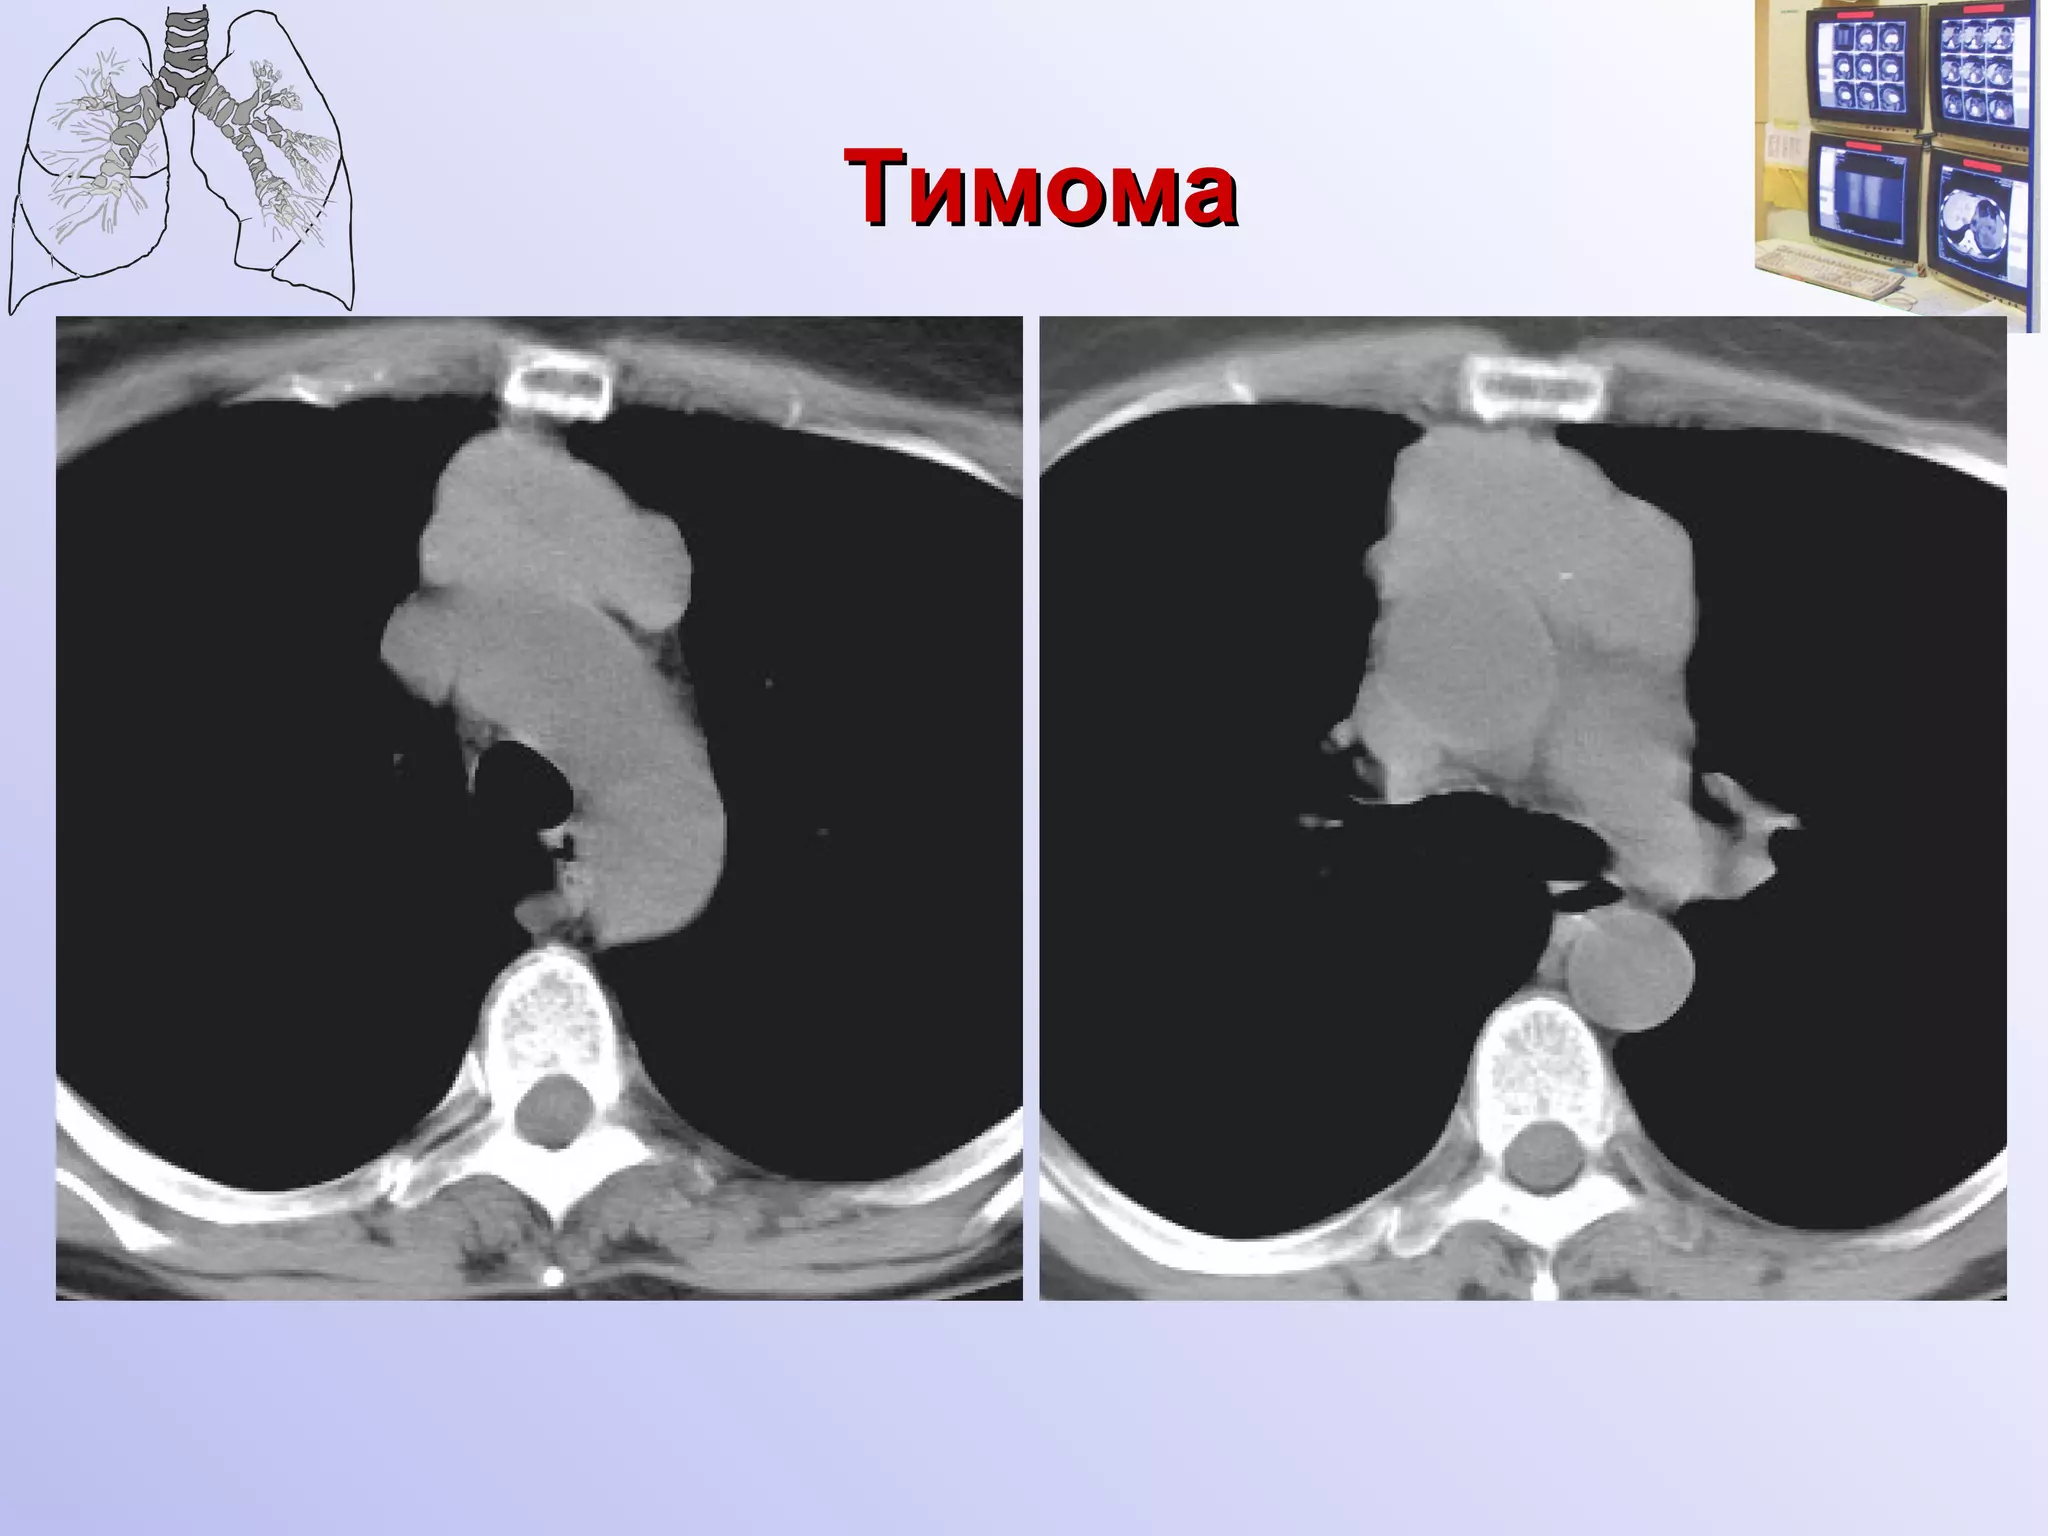

Рентгенологическая и КТ семиотика доброкачественных тимом Локализуется асимметрично в среднем этаже переднего средостения  При глотании не смещается Форма овоидная, неправильно шаровидная, грушевидная  Сплющена в передне-заднем размере, прижата к грудине Поверхность бугристая, контуры четкие Структура однородная, известковые включения встречаются крайне редко Отграничена капсулой

Тимома

Рентгенологическая и КТсемиотика доброкачественных тимом Локализуется асимметрично в среднем этаже переднего средостения При глотании не смещается Форма овоидная, неправильно шаровидная, грушевидная Сплющена в передне-заднем размере, прижата к грудине Поверхность бугристая, контуры четкие Структура однородная, известковые включения встречаются крайне редко Отграничена капсулой

• 11.